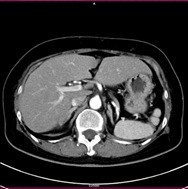

胸部CT画像 腹部CT画像

CT検査には、そのまま検査台に寝ていただき撮影する単純CTと造影剤を用いた造影CT検査があります。基本的には単純CT検査を行った後、より詳細に観察したい場合や血管などを観察する場合に行います。造影CT検査は肘(ひじ)のあたりに針を刺し血管内(静脈)に造影剤を入れて撮影します。

単純CT画像 造影CT画像 MPR画像